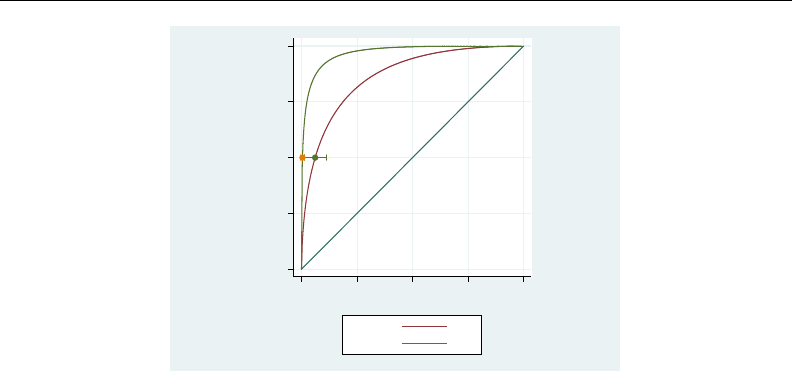

- roc

- roccomp

- rocfit

- rocfit postestimation

- rocreg

- rocreg postestimation

- rocregplot

- roctab